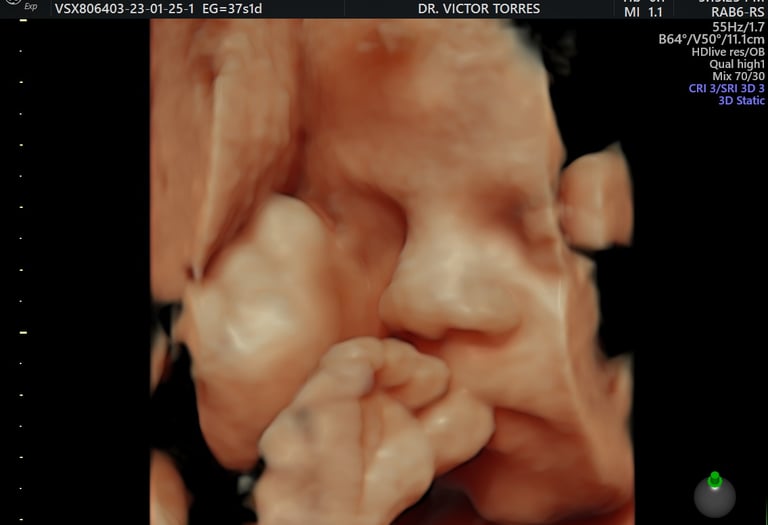

Dr. Victor Torres C.

Ginecólogo-Obstetra | Medicina Fetal

• Posgrado en Medicina Fetal por Fetal i+D Education Barcelona.

• Fellow en Cardiología Fetal por la Fundación Internacional de Medicina Materno Fetal.

• Más de 10 años de experiencia en el cuidado de la salud femenina y materno-fetal.

• Entrenamiento en Ginecología Laparoscópica, Ecografía Gineco-Obstétrica y Cuidados Intensivos Maternos en centros de referencia en Perú y México.

• Auditado y con licencias por The Fetal Medicine Foundation.

Galería